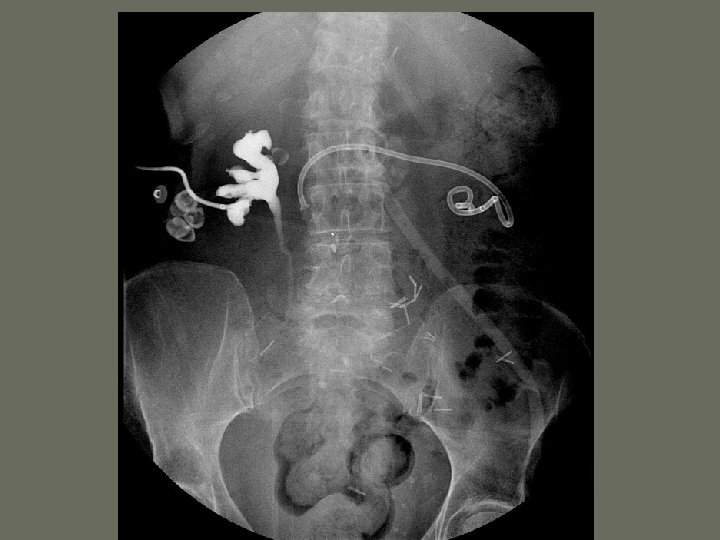

Interventional Procedures • Non-vascular procedures include: 1. Percutaneous Nephrostomy Tube – catheter is introduced through the _____, into the kidney and into the renal pelvis – may be used to remove _____, drain fluid or other interventions

Interventional Procedures 2. Percutaneous Biliary Drainage • internal or external drainage of ______, stone removal, dilation of obstructed bile duct and biopsy • catheter placed within the biliary ____ with a bag attached to the catheter outside the body

Interventional Procedures 3. Percutaneous Abdominal Abscess Drainage • indicated if a simple incision cannot be performed • abscess needs to be in a safe area for a _____ placement

Interventional Procedures 4. Percutaneous Gastrostomy • performed for extended _______ of patients unable to eat, gastric decompression, or dilation of upper GI tract • indicated for patients who cannot _______ due to a variety of reasons

Interventional Procedures 5. Percutaneous Needle Biopsy • suspicion of primary or _______ malignancy • portion of the infected tissue is removed for testing

Interventional Procedures 6. Ureteric Stent Placement • Inserted in ureter • performed after a percutaneous nephrostomy • used on patients with ________ of the renal system

Interventional Procedures 7. Percutaneous Lithotripsy • extracorporeal shock wave lithotripsy (ESWL) • renal stone is obliterated until they are ______ enough to pass through the urinary system